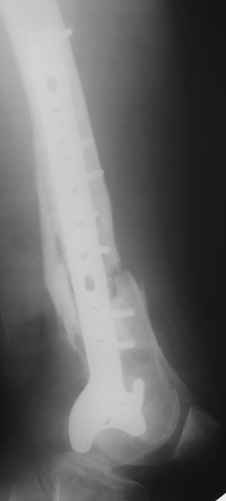

Обратился на консультацию больной. 24 декабря 2009г. попал в ДТП, получил переломы правого бедра, правой ключицы и  левой голени. 28 января 2010г. выполнен металлоостеосинтез правой бедренной кости пластиной. 8 апреля 2010г. выявлен неполный перелом пластины, на половину, по одному из отверстий для винтов. 15 апреля 2010г., на фоне сепсиса, выполнен реостеосинтез со свободной костной аутопластикой зоны перелома. Ранний послеоперационный период осложнился нагноением гематомы в месте операции. Последняя была эвакуирована с сохранением фиксатора. Рана зажила. Через два месяца открылся свищ с незначительным слизисто-гнойным отделяемым, функционирует до сих пор без изменений. При осмотре – в центре послеоперационного рубца свищ, около 2 мм в диаметре, со скудным отделяемым. Зонд, введенный в свищевой ход, доходит до металлоконструкции. Коленный сустав отечный, активные и пассивные движения в нем резко ограничены и составляют: сгибание – 100 градусов, разгибание – 160. Выполнили рентгенографию – ложный сустав, остеомиелит, пластина установлена слишком низко, «внутрисуставно», что вызывает постоянный синовиит и отек параартикулярных тканей.

Хотелось бы обсудить тактику дальнейшего лечения:

1.      Считаем, что у молодого человека, милиционера по профессии,  спасти коленный сустав другими способами, кроме БИОС, маловероятно.

2.      Чему отдать предпочтение – обычный вариант или ретроградный?